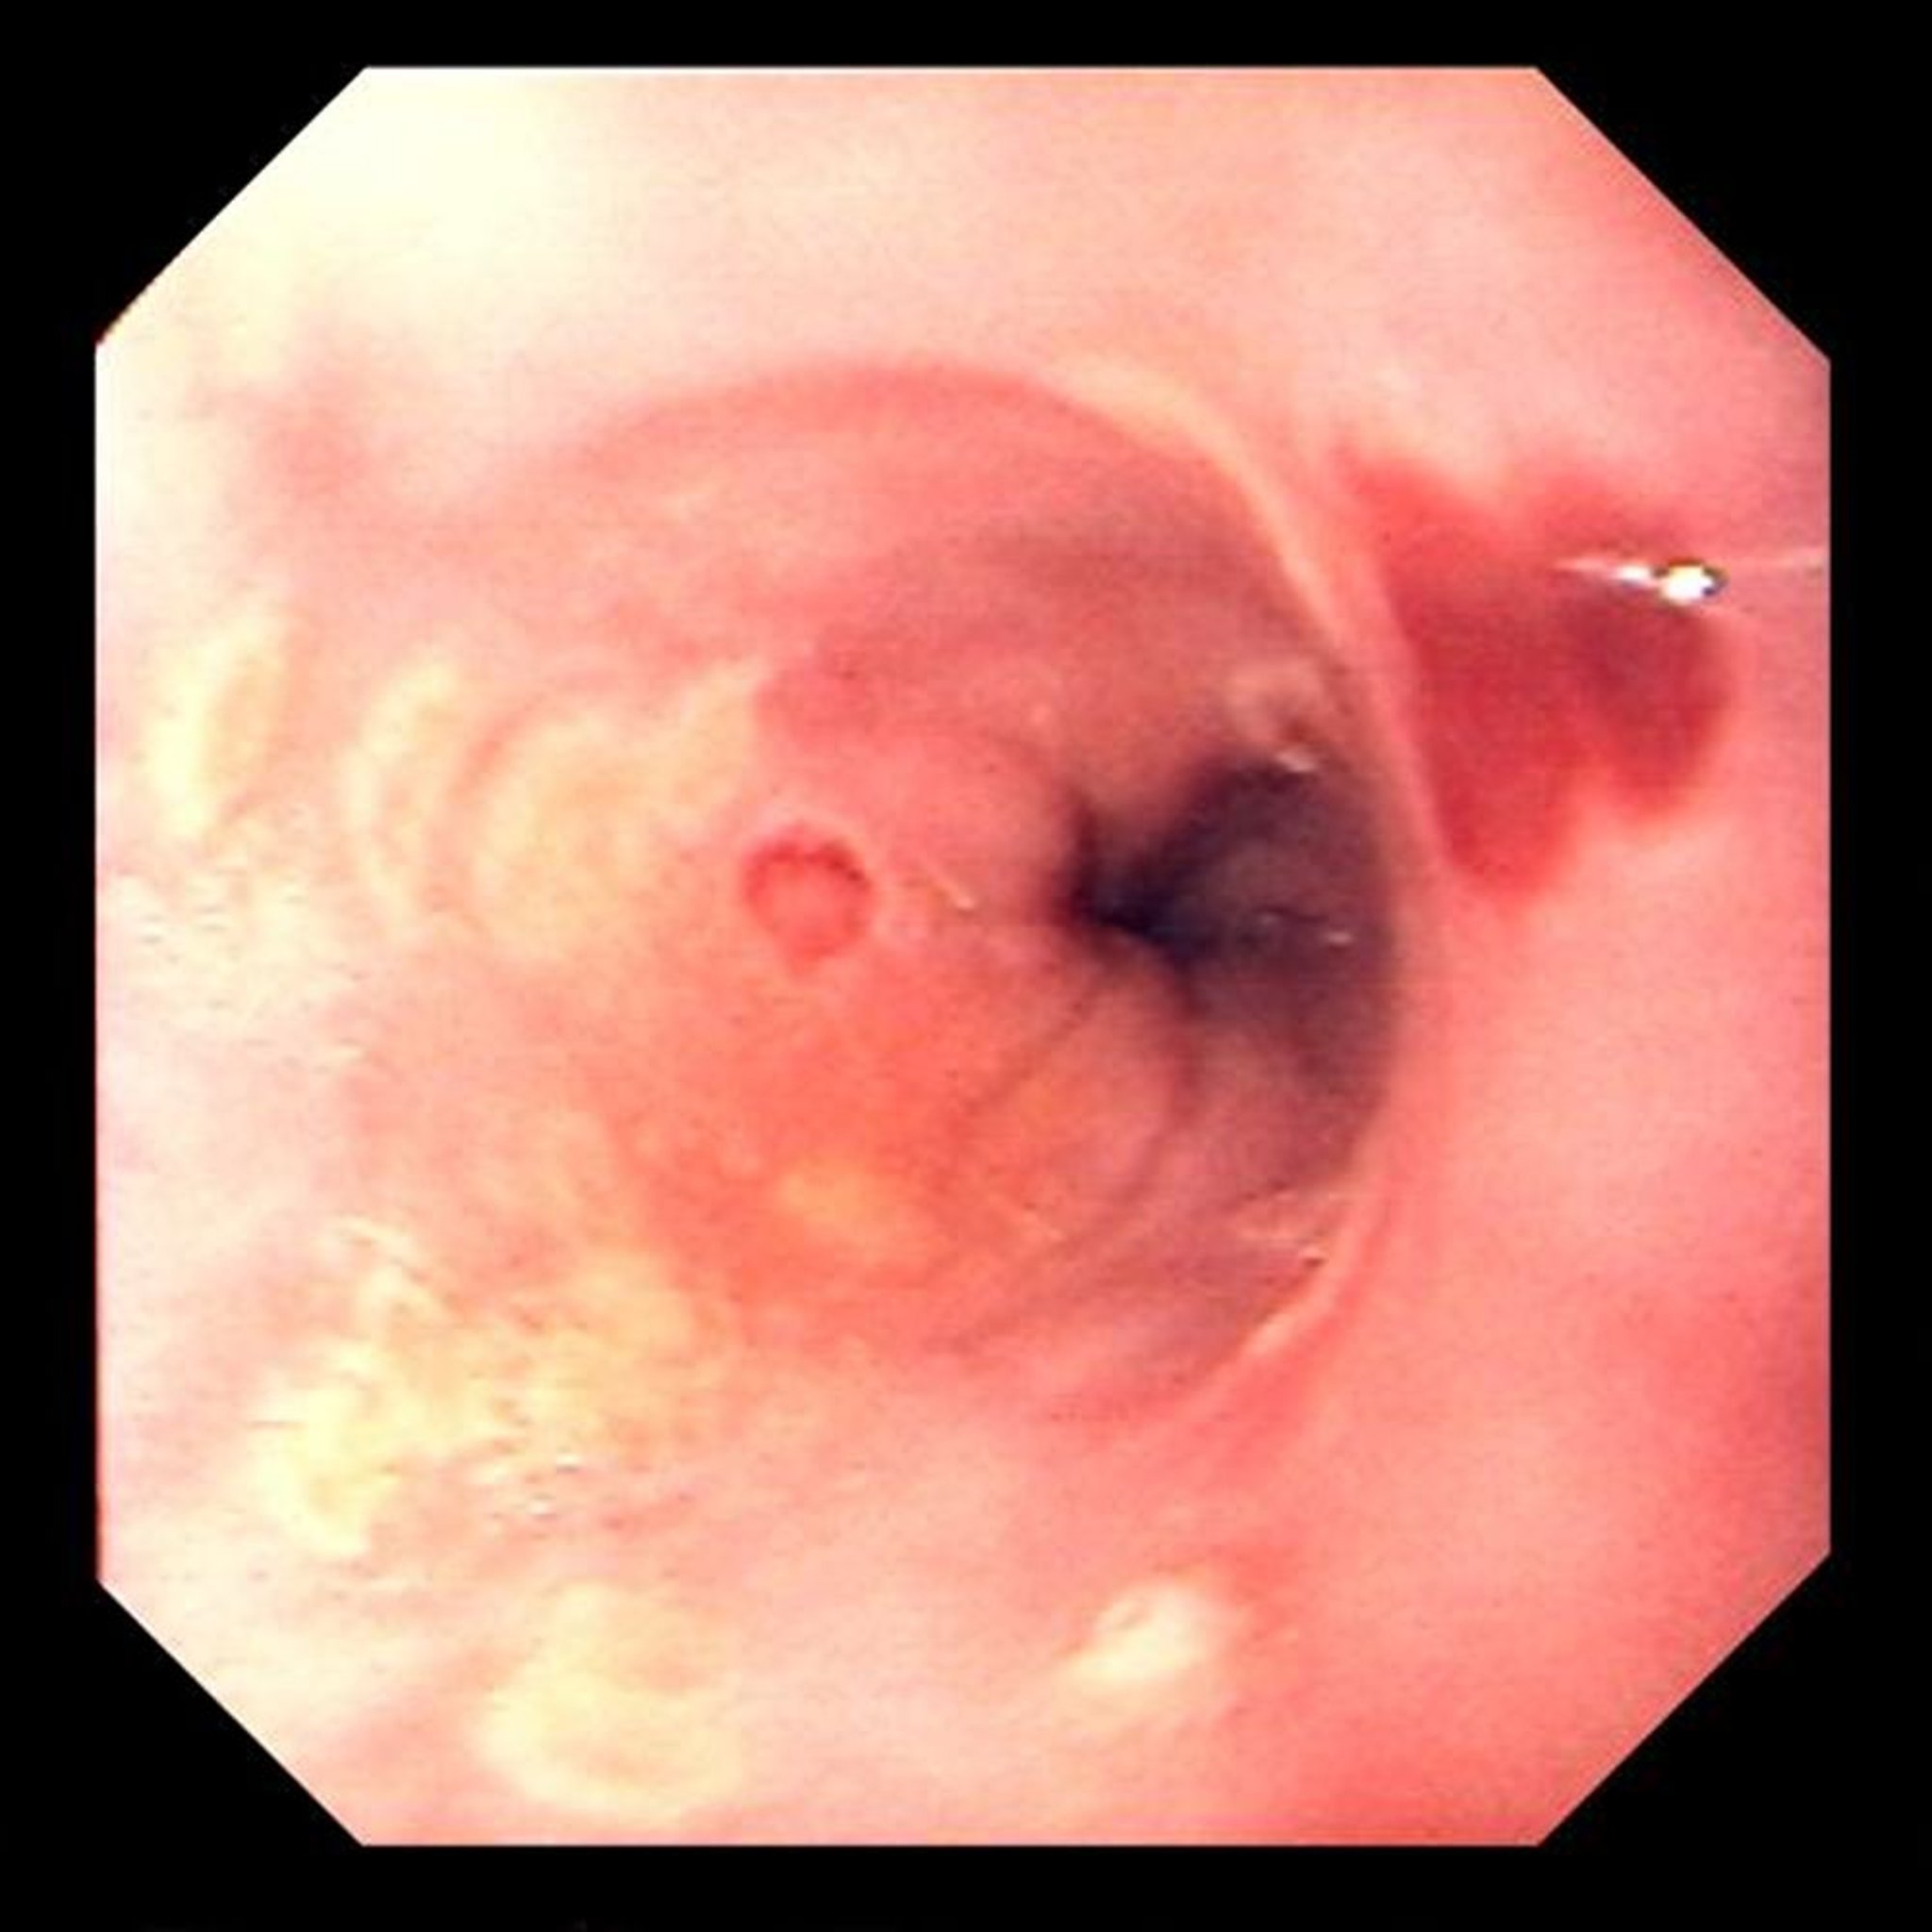

Viêm thực quản do Herpes Simplex

Loét khu trú là điển hình của viêm thực quản do vi rút herpes simplex.

Hình ảnh do bác sĩ David M. Martin cung cấp.